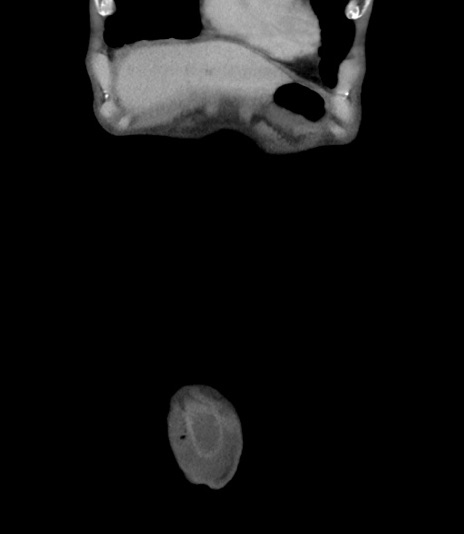

矢状断像